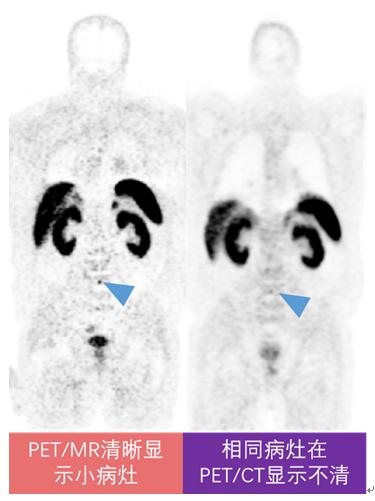

尽管PET/CT和PET/MR都有PET,但是PET/MR的功能更加强大、敏感度更高。PET/MR采用的PET设备更加先进,能发现更多PET/CT上隐匿的小病灶。众所周知,人体的呼吸、心跳等运动会对影像诊断造成很大干扰,使得PET影像和CT图像匹配不准;而PET/MR采用了更先进的技术,克服了呼吸、心跳的干扰,图像匹配更精准。